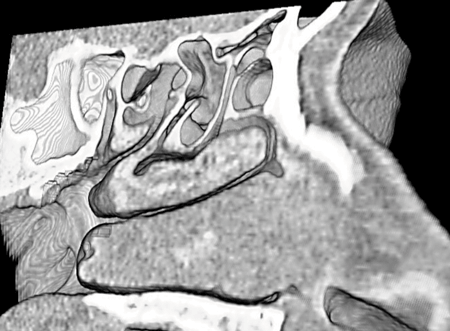

Evolution of sinus imaging: (Figure A) X-ray polytomography; (Figure B) Coronal CT scan; (Figure C) CT MPR and surface-rendered 3D image; (Figure D) 3D CT Stereoscopic Image showing the anatomy in the sagittal plane.

At the Endo Chicago 2016 meeting, Dr Stammberger and I discussed the need to establish imaging landmarks based on the lamellar principles that were the subject of his lectures. The discussion continued in Stockholm at the ERS meeting, and then later, at the AAO-HNS meeting, that same year. By the time we met in San Diego, I was able to show him preliminary 3D CT stereoscopic images we were creating at Hopkins. He was amazed, as he looked at the 3D stereographic images that provided information which, for the first time, resembled the actual anatomy. As we studied the images, he was convinced that the new technology would provide a new look and an improved understanding of the individually complex sinus anatomy.

For two years, we continued to re-study the anatomy, with the help and contributions of Meiyappan Solaiyappan, Dr Bill Bolger, and Dr Masaru Ishii, who completed our team. Our work and discussions focused on a plan that we would follow to publish this information. Unfortunately, on December 9, 2018, Dr Stammberger was taken from us all. He was ‘the wind behind the sails’ of our team. His fund of knowledge, expertise, and keen observational capability provided the foundation for the work we are about to start disseminating.